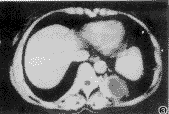

胸部CT检查: 平扫示左肺下叶后基底段主动脉旁一类圆形肿块,最大径约6.5cm,有包膜,其内低密度,均匀,CT值为15HU(图1)。增强扫描示包膜强化,但其内低密度处不强化,并见胸主动脉左后方有一分支伸向肿块(图2、3)。CT诊断为左肺下叶肺隔离症。

图2 CT增强扫描示左下肺后基底段肿块的下极部分,包膜强化,其内低密度不强化,并见胸主动脉有一分支伸向肿块(↑)

图3 CT增强扫描(图2的上一层面)示肿块之包膜及进入肿块的血管强化